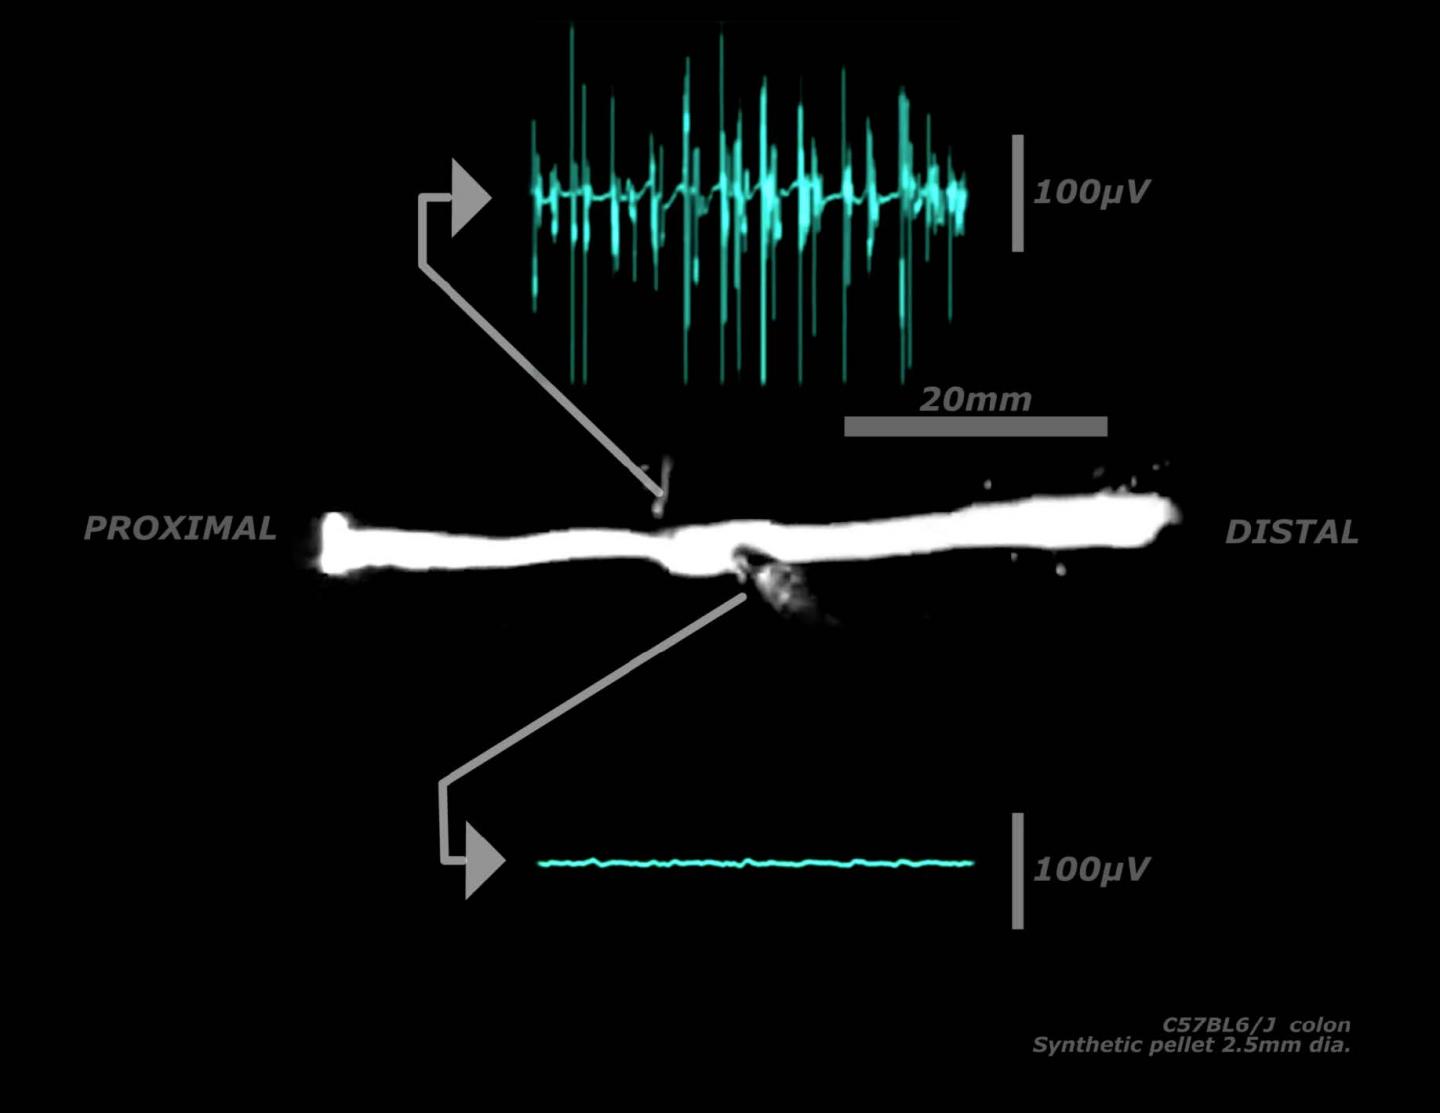

Nick Spencer and colleagues combined a new neuronal imaging technique with electrophysiology records of smooth muscle to reveal a pattern of activity that involves many different types of neurons firing simultaneously in repetitive bursts to activate the muscle cells at the same rate. They demonstrate how this rhythmic activity generates so-called colonic migrating motor complexes to transport fecal pellets through the mouse colon. These findings identify a previously unknown pattern of neuronal activity in the peripheral nervous system.

Millions of neurons in the gastrointestinal tract coordinate their activity to generate the muscle contractions that propel waste through the last leg of the digestive system, according to a study of isolated mouse colons published in JNeurosci . The newly identified neuronal firing pattern may represent an early feature preserved through the evolution of nervous systems.